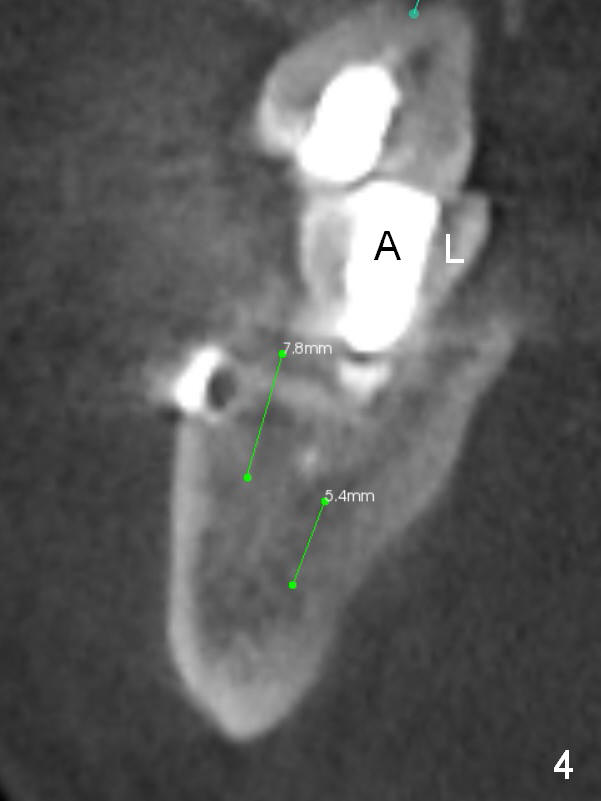

A 39-year-old man (ZC) fractures the lingual portion of the tooth #31 while eating peanut during Christmas (Fig.1 green arrows), a few months finishing #28,29 implant crowns. It fractures between the large amalgam (Fig.3 A) and the lingual portion of the tooth (L). It should be subgingival and nonsalvageable. Prepare crown prep or immediate implant. If the latter is indicated, the socket will be treated with 2% Xylocaine/1:50,000 Epinephrine. The distance between the apex of the socket and the Inferior Alveolar Canal is >5 mm (Fig.2,4). If osteotomy is controlled 3 mm beyond the apex of the socket, it is safe (Fig.3,5). A 5.9x10 or 12 mm implant should be able to engage to the buccal and lingual walls for additional stability (Fig.5), while there will be mesial and distal gaps to be filled with bone graft (Fig.3 red dots).